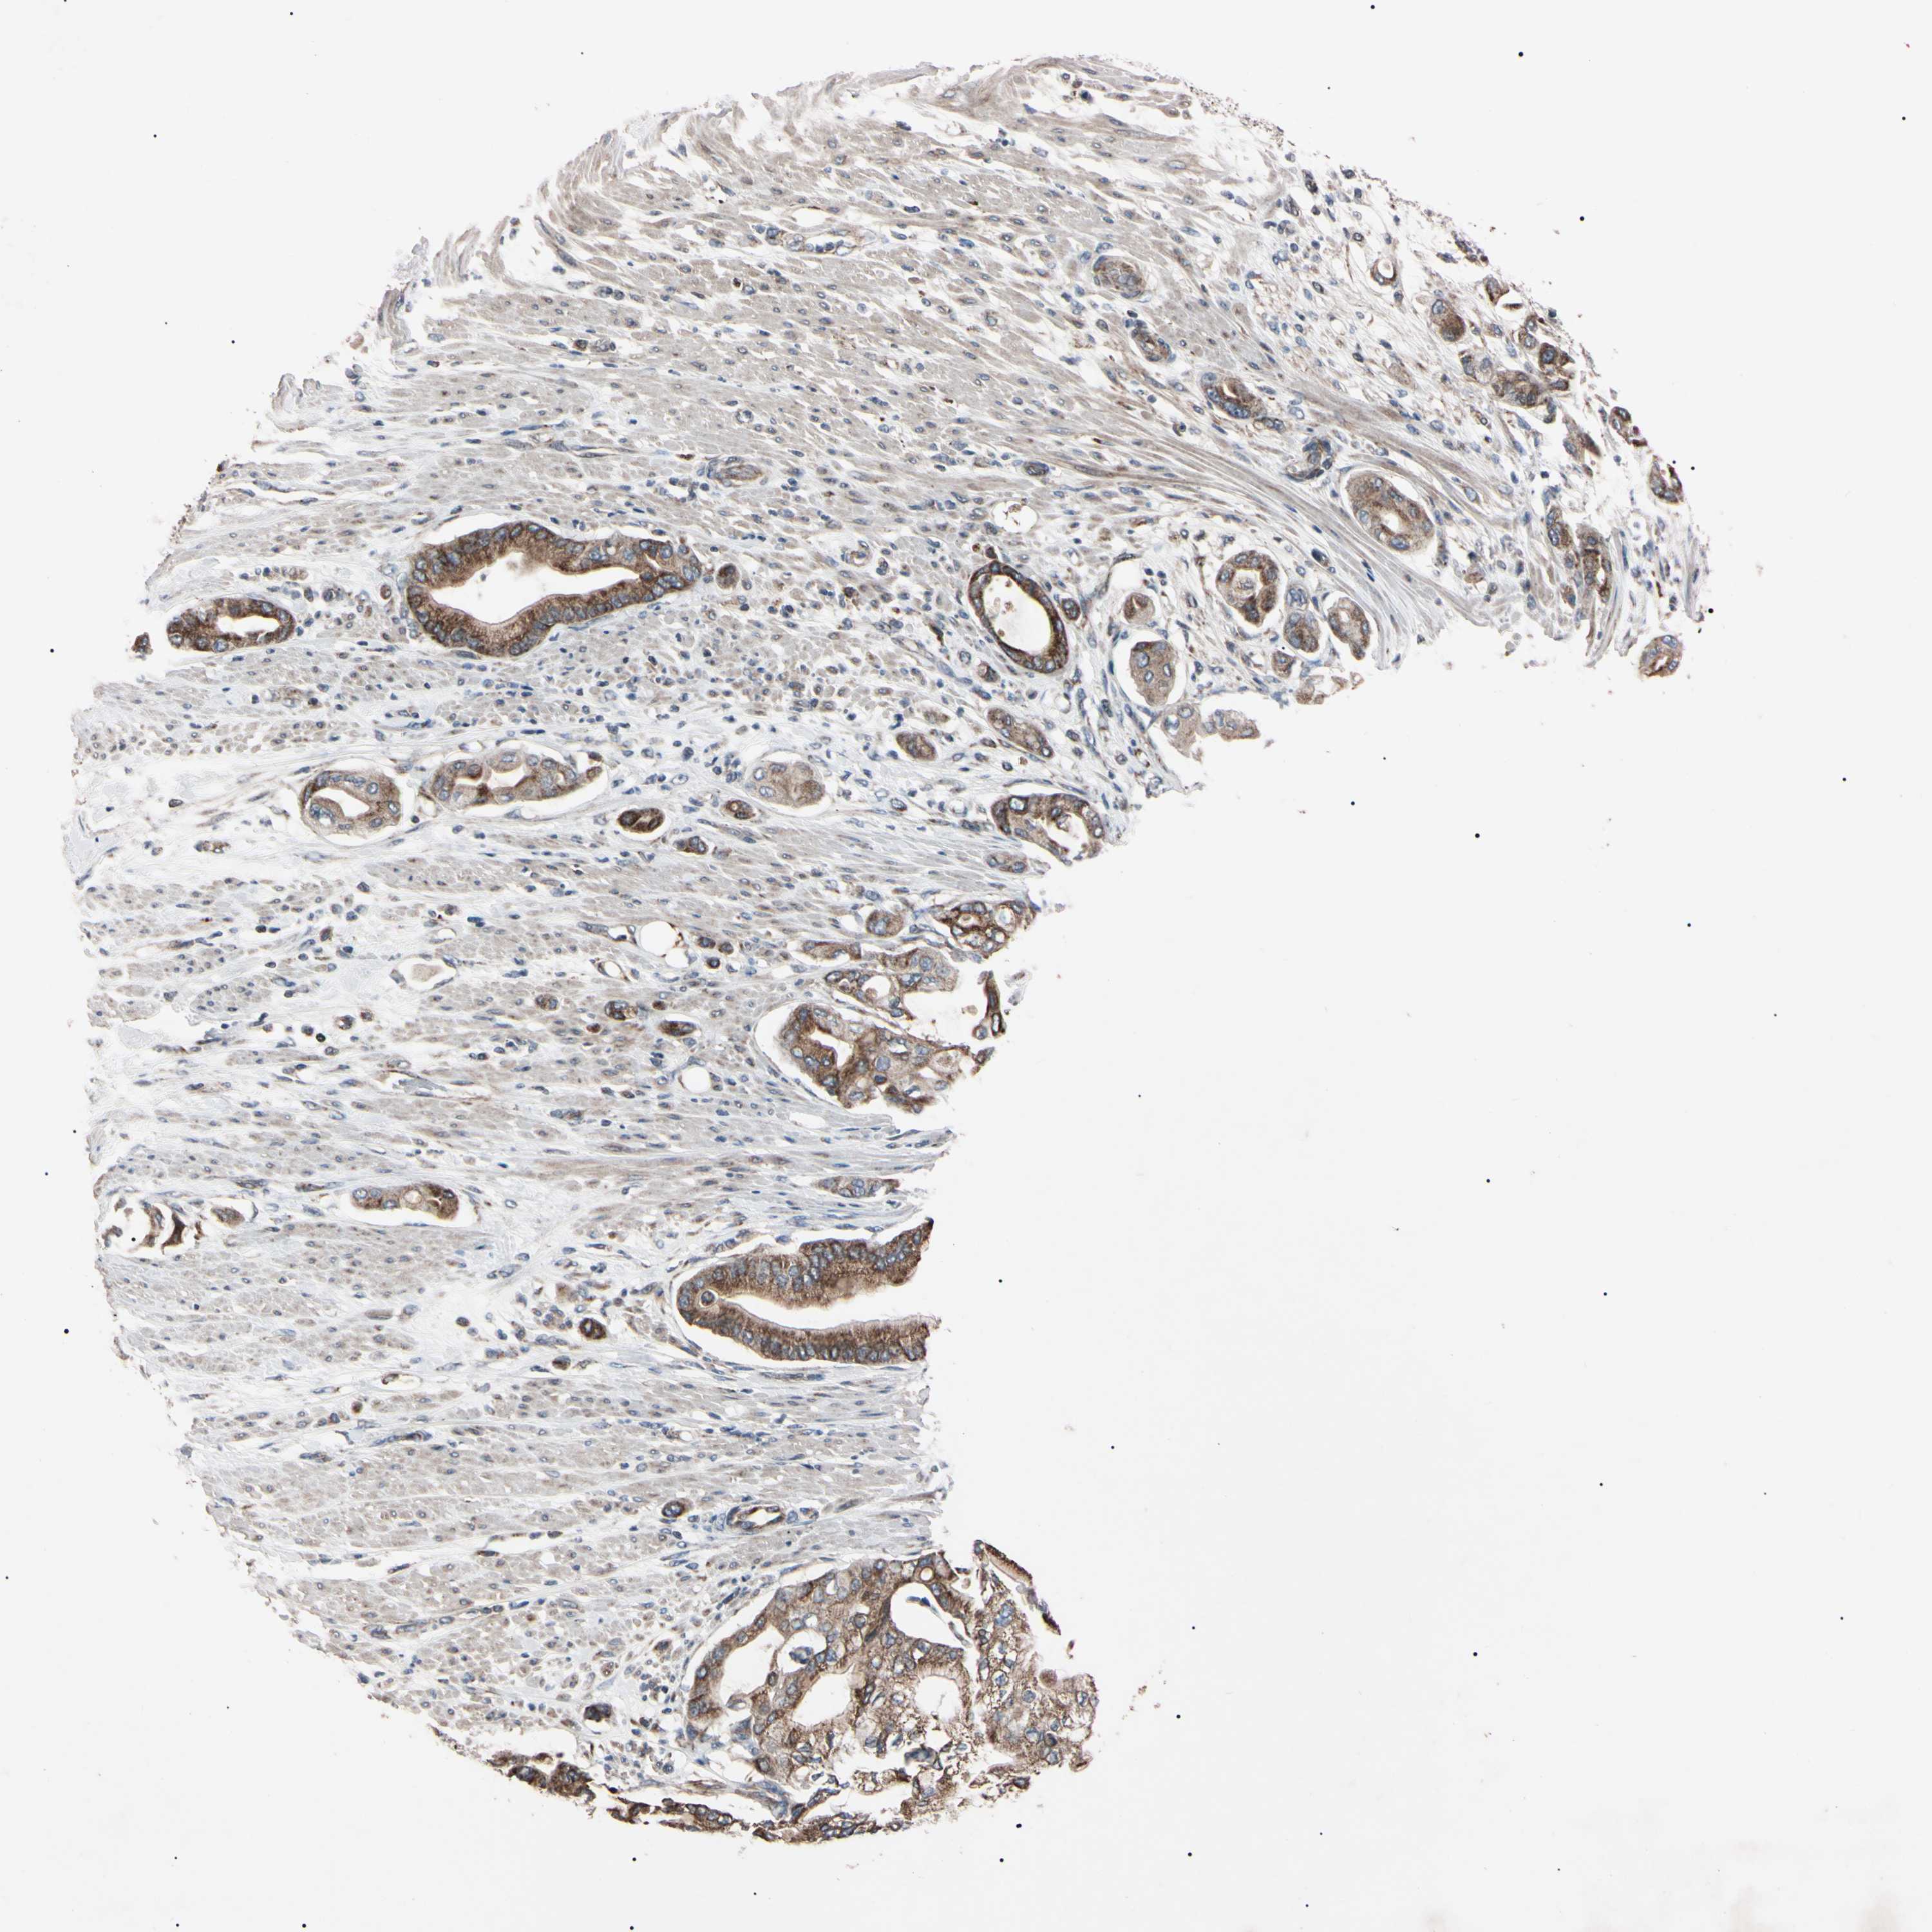

PANCREATIC CANCER - Protein expressioni

A mouse-over function shows sample information and annotation data. Click on an image to view it in a full screen mode. Samples can be filtered based on level of antibody staining by selecting one or several of the following categories: high, medium, low and not detected. The assay and annotation is described here.

Note that samples used for immunohistochemistry by the Human Protein Atlas do not correspond to samples in the TCGA dataset.

Antibody stainingi

Antibody staining in the annotated cell types in the current human tissue is reported as not detected, low, medium, or high, based on conventional immunohistochemistry profiling in selected tissues. This score is based on the combination of the staining intensity and fraction of stained cells.

Each image is clickable and will lead to virtual microscopy that enables deeper exploration of all samples and also displays staining intensity scores, fraction scores and subcellular localization as well as patient and tissue information for each sample.

Antibody HPA004102

Antibody CAB010309

Staining

High

Medium

Low

Not detected

Intensity

Strong

Moderate

Weak

Negative

Quantity

>75%

75%-25%

<25%

None

Location

Nuclear

Cytoplasmic/membranous

Cytoplasmic/membranous,nuclear

Adenocarcinoma, NOS

Adenocarcinoma, metastatic, NOS